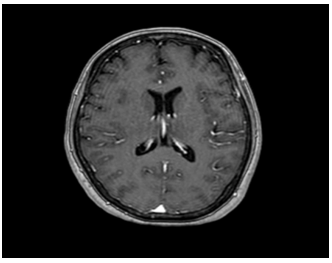

Hình 5: Hình ảnh cộng hưởng từ sọ não: chưa phát hiện tổn thương thứ phát

– Cộng hưởng từ sọ não: Không phát hiện tổn thương bất thường.